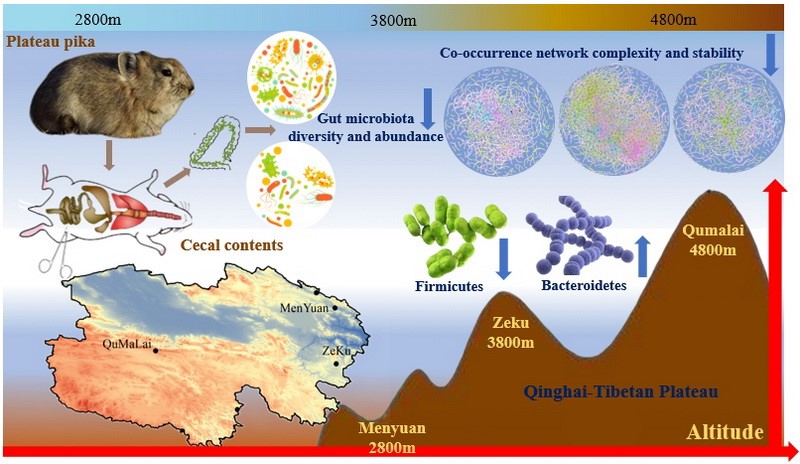

![]() پیشرفت تاریخی در فناوری رابط مغز و ماشین؛ رمزگشایی همزمان زبان و حرکت در زمان واقعی

پیشرفت تاریخی در فناوری رابط مغز و ماشین؛ رمزگشایی همزمان زبان و حرکت در زمان واقعی